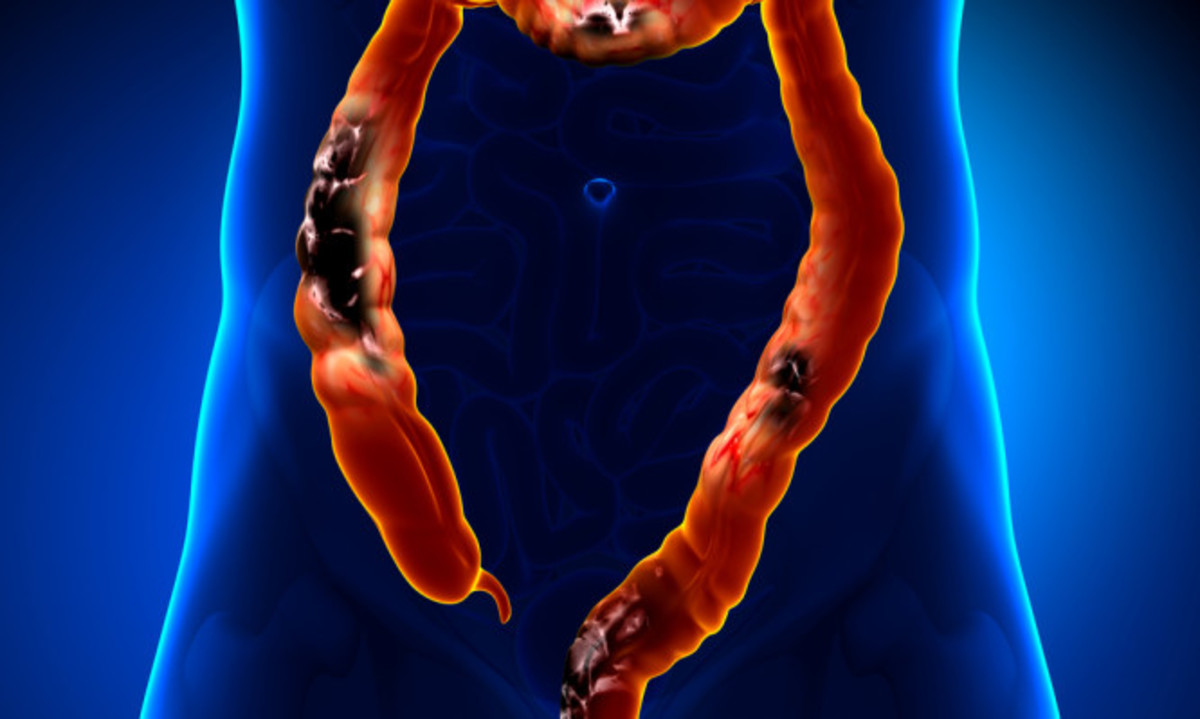

Οι πολύποδες μπορεί να προκαλέσουν συμπτώματα, τα οποία, ωστόσο είναι πολλές φορές πολύ ήπια και δεν γίνονται εγκαίρως αντιληπτά. Για το λόγο αυτό, οι γιατροί συστήνουν τακτικές εξετάσεις προσυμπτωματικού ελέγχου για την έγκαιρη πρόληψη του καρκίνου του παχέος εντέρου, μέσω του ελέγχου των πολυποδών πριν εξελιχθούν σε καρκίνο του παχέος εντέρου.